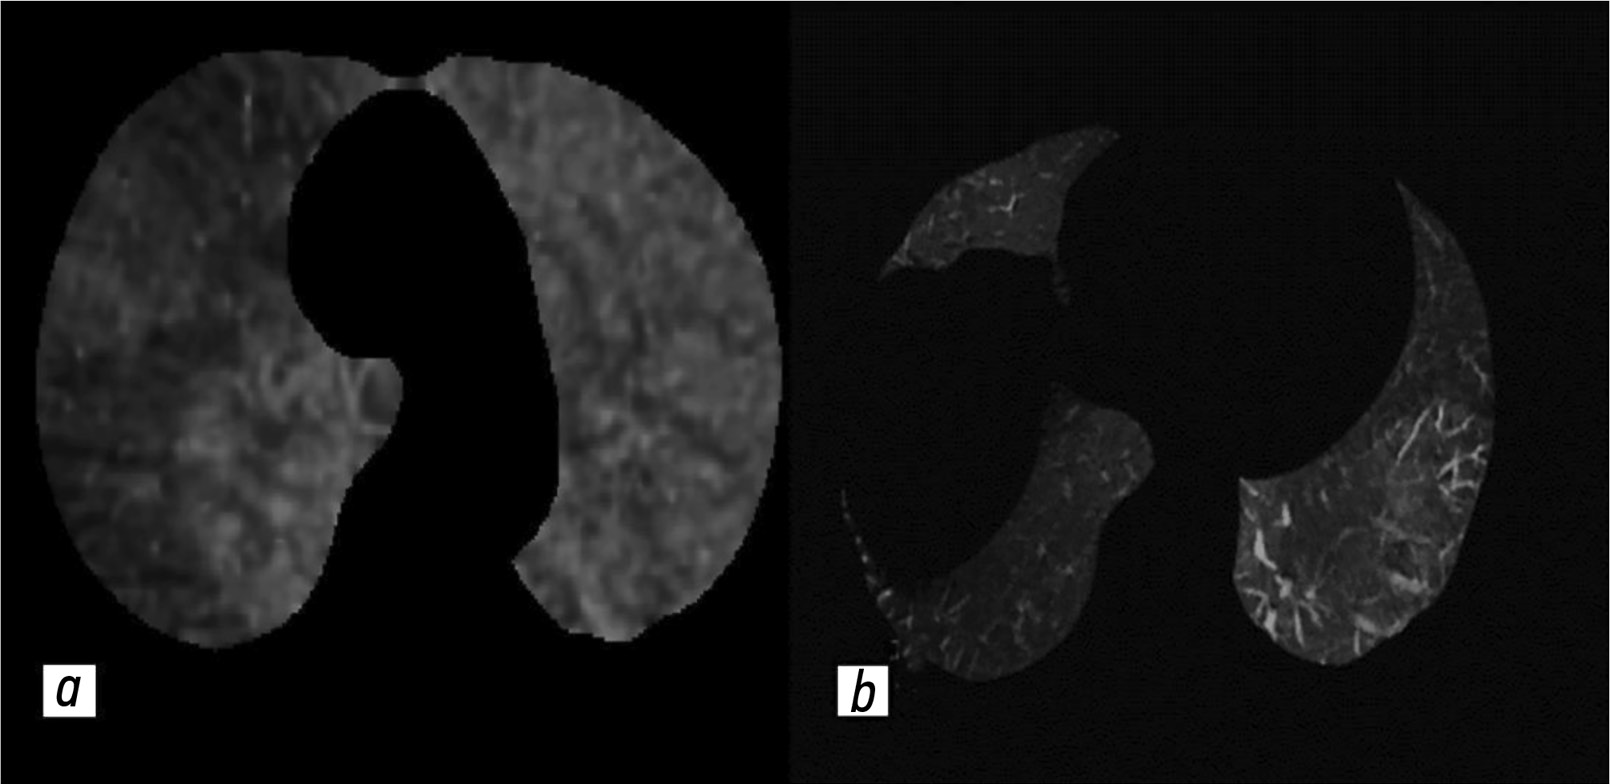

На изображениях с выделением сосудов отчётливо визуализируются лёгочные артерии с высокой контрастностью и меньшим шумом, что позволяет идентифицировать артерии мелкого калибра. На реконструкциях с выделением лёгочной паренхимы сосуды определяют как тёмные участки, соответствующие бассейнам окклюзированных артерий (рис. 5).

Рис. 5. Субтракционные изображения паренхимы и сосудов: a — тёмный участок в правом лёгком, визуализируемый в режиме Sub-Lung, соответствует пониженной перфузии в лёгких; b — нитевидные лёгочные артерии, визуализируемые в режиме Sub-VSL. Публикуется с разрешения правообладателя. © ФГАУ «Лечебно-реабилитационный центр», 2018.